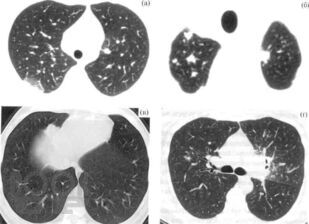

В учебно-методическом пособии авторы представили данные об этиологии, патогенез, патологической анатомии саркоидоза, клинико-рентгенологические классификации, методы диагностики лабораторные, лучевые (рентгенография, томография, КТ, МРТ, ПЭТ), радиоизотопное, бронхологические особенности современного саркоидоза. Приведены примеры собственных наблюдений.